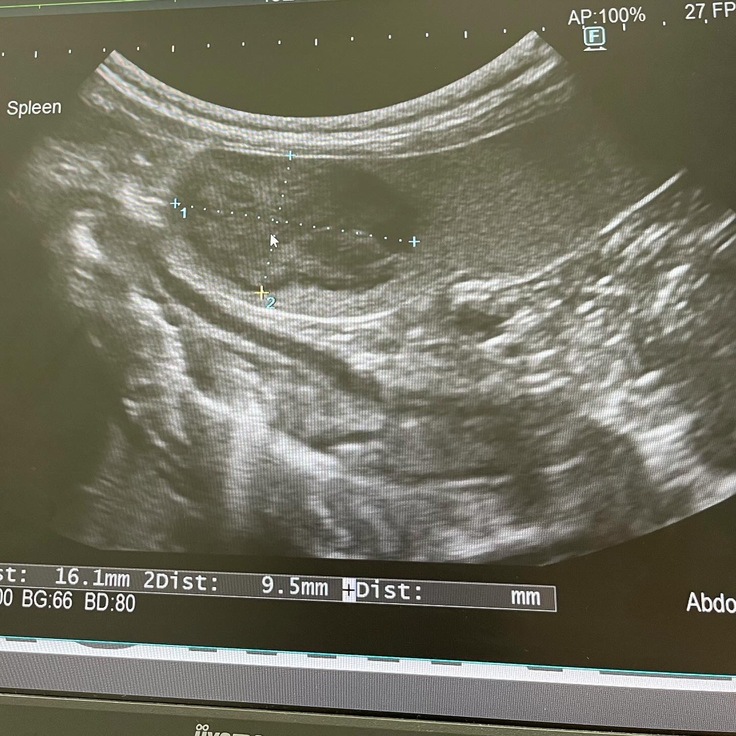

2022.02に脾臓に小さな腫瘍があると

※この時のサイズは縦横1cmでした。

2023.11に手術をお願いしている

循環器専門動物病院さんにて

僧帽弁閉鎖不全症の術前検診で

脾臓の腫瘍の事について再度診断が出ました。

※この時のサイズは縦1cm 横1.61cmでした。

細胞診と言う針で細を刺しての

2023.11.15に細胞診をお願いしました。

細胞診では、良性なのか、悪性なのかの判断は

100%は出ないので

最終的には脾臓の全摘出の手術を

する事になります。

細胞診の結果では″リンパ腫の疑い″

との診断でした。